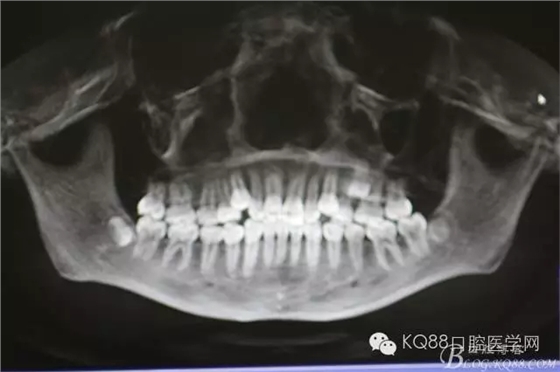

圖1.術(shù)前口內(nèi)頰側(cè)觀:24與26鄰接正常,頰側(cè)黏膜平整、無(wú)隆起。

圖3.術(shù)前的CBCT檢查:全景片重建影像,25位于24與26牙根的中1/3處。